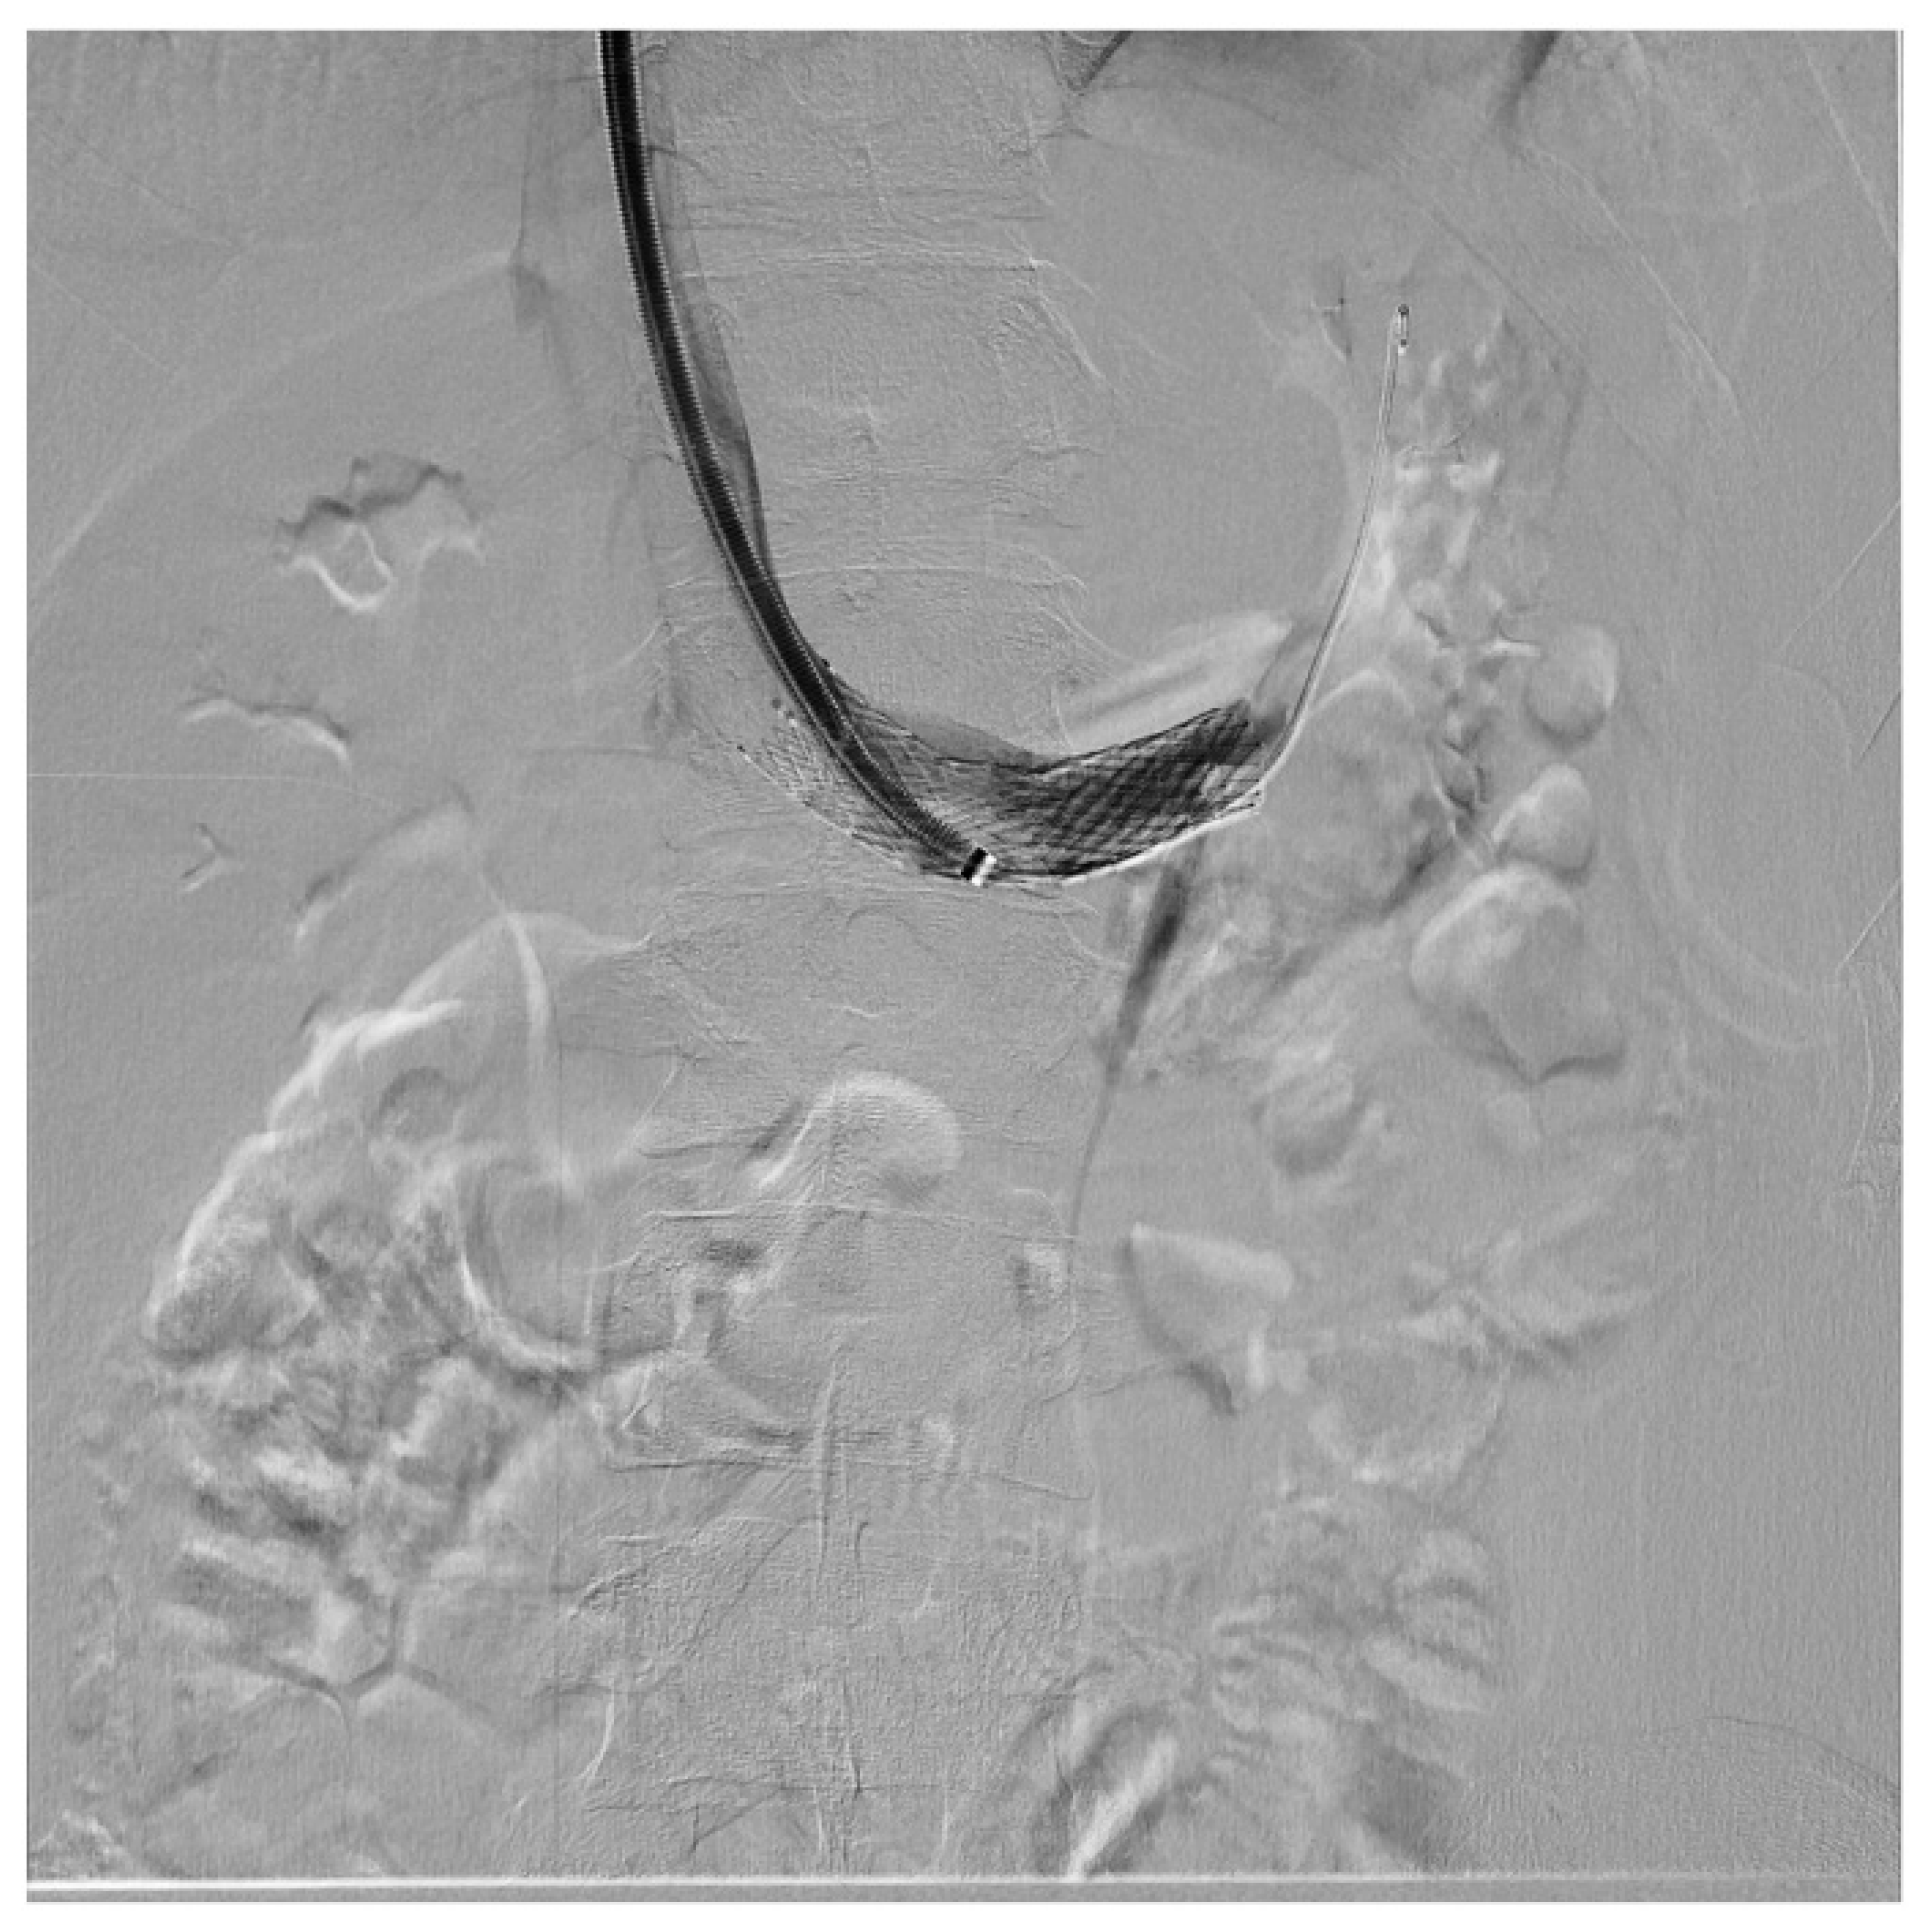

Computed tomography (CT) revealed the nutcracker phenomenon and Nutcracker Phenomenon Nutcracker syndrome is a vascular compression disorder that affects the left renal vein, causing hematuria and other symptoms. Learn about the causes, symptoms, diagnosis, and treatment of nutcracker phenomenon and syndrome,. Nutcracker syndrome (ns) is a condition in which two arteries compress the left renal vein, affecting blood flow out of the left kidney. Nutcracker syndrome (ncs) is an extrinsic. Nutcracker Phenomenon.